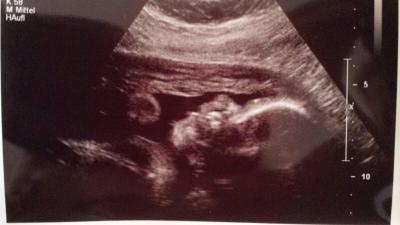

Leider leider weiß ich noch immer nicht was es wird :/ es zeigt sich null,ABER wenigstens gabs Füße und Hände zu sehen UND sogar das Gesicht anbei das Profilbildchen meines Bauchbewohners ;) zumindest wenns klappt mit dem hochladen ^^

Bild zu Bericht von heute + Bild - Forum für August - Mamis

aber trotzdem niedliches Bildchen lg